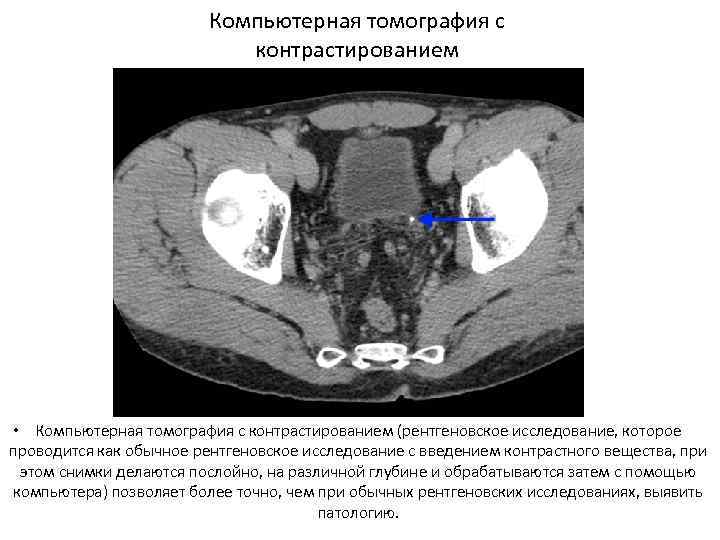

Диагностика • Анализ анамнеза заболевания и жалоб. • Анализ анамнеза жизни. • Данные врачебного осмотра (положительный симптом поколачивания — боль при легких ударах в поясничной области). • Анализ крови — сдвиг лейкоцитарной формулы влево, повышение СОЭ (скорость оседания эритроцитов, неспецифический признак воспаления). • Анализ мочи — появляются эритроциты, единичные цилиндры (своего рода слепки канальцев почек, которые состоят из свернувшихся в кислой среде мочи белков и других компонентов, важный признак почечной патологии) и соли, лейкоцитурия (обнаружение лейкоцитов в моче — признак воспаления) Эндоскопические методы: • Цистоскопия • УЗИ Рентгенологические методы: • обзорная рентгенография брюшной полости • экскреторная урография • Динамическая сцинтиграфия • Компьютерная томография с контрастированием

КТ Компьютерная томография с контрастированием • Компьютерная томография с контрастированием (рентгеновское исследование, которое проводится как обычное рентгеновское исследование с введением контрастного вещества, при этом снимки делаются послойно, на различной глубине и обрабатываются затем с помощью компьютера) позволяет более точно, чем при обычных рентгеновских исследованиях, выявить патологию.